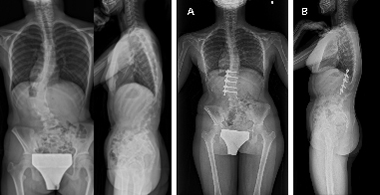

前方後方矯正固定術

せぼねが大きく変形している場合や再手術の際に前方手術と後方手術を両方行って、せぼねの矯正と固定を行います。

1日で両方の手術を行う場合と2日間に分けて手術を行う場合があります。大人の患者様では3週間程度で場合によってはリハビリテーション病院へ転院をしていただき、さらにリハビリテーションを行います。